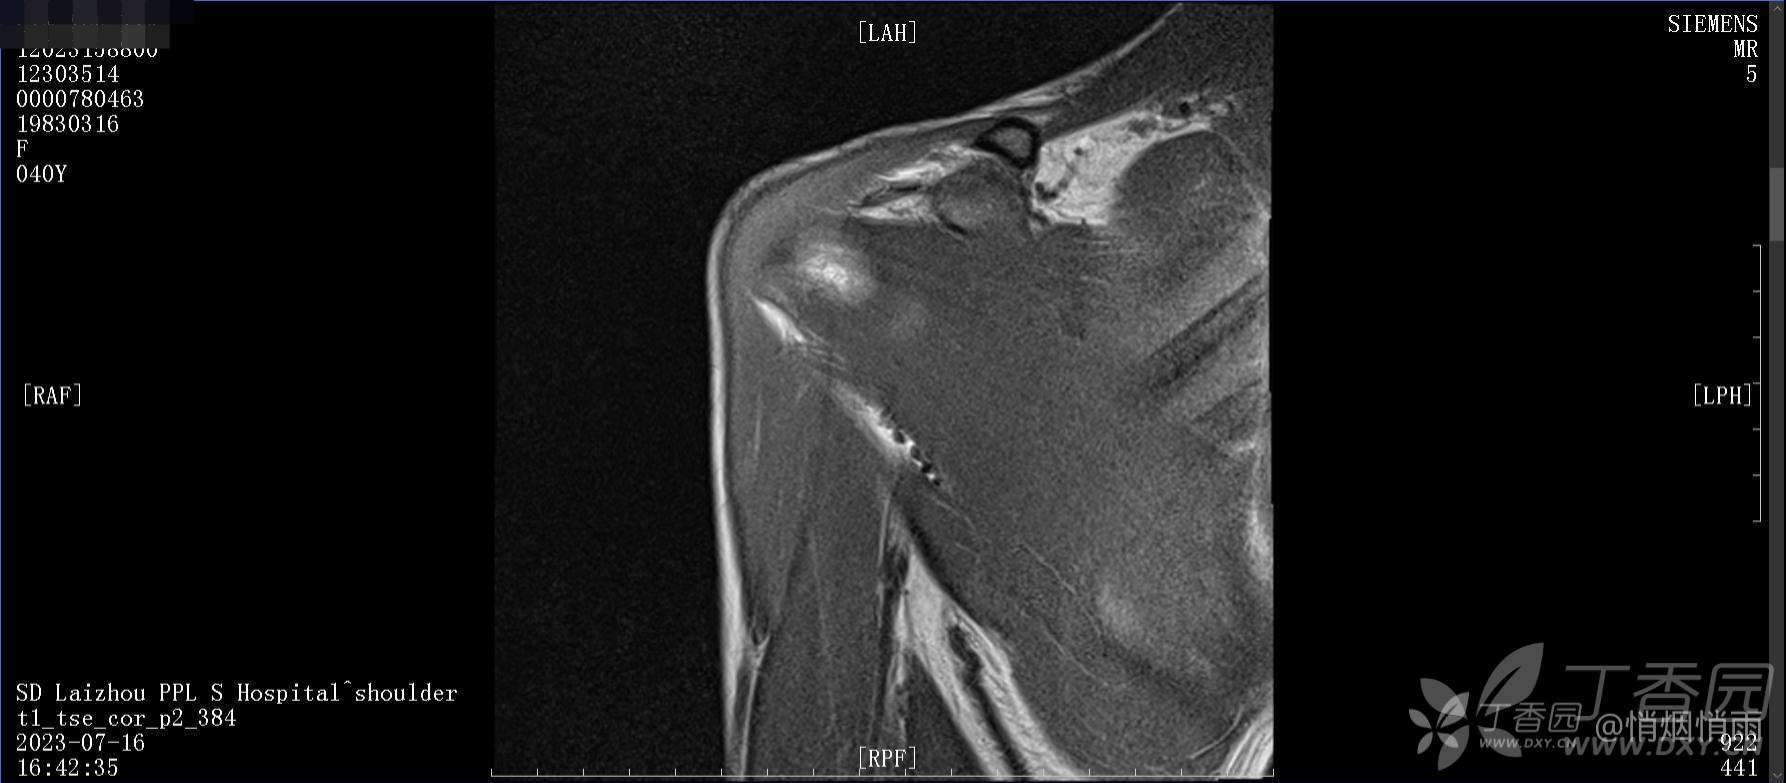

查体:右肩关节局部轻度肿胀,肩胛区压痛明显,痛处不固定,肩关节痛性活动受限,jobe test(+),lift -off test(+),中指、环指感觉较余指减退,余肢端感觉及血运情况可。

目前的诊断,暂时依据辅助检查诊为肩袖损伤,但是患者疼痛的性质和特点,却不是单纯的肩袖损伤所致。考虑过胸廓出口综合征,但是该疾病会出现肩胛区的疼痛吗?(由于考虑到费用的问题,没再进行下一步的检查)带状疱疹会有如此的症状吗?